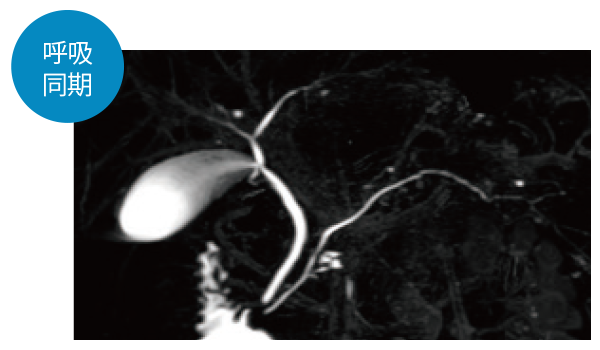

IP-RAPID×DLR Plusによって呼吸同期計測や横隔膜同期計測など時間のかかる検査を短くできます。さらに時間を短くし、息止めによる検査に変更することもでき、患者さまの状況に合わせて検査をお選びいただけます。選択肢が増えるので、検査の幅が広がります。

3DMRCP(息止め)

3DMRCP横隔膜同期(Navi)

3DMRCP(呼吸同期)